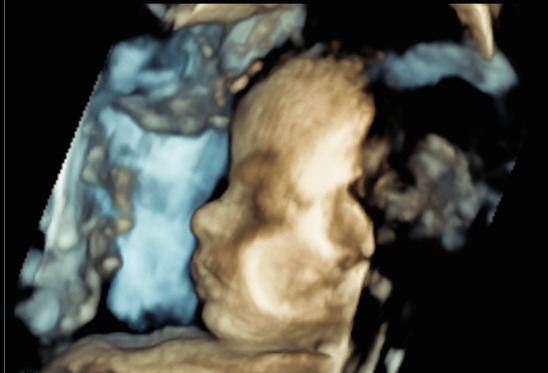

The scan time can vary depending on how baby is positioned in the uterus and the difficulty of the scan. The NCDI can allow one hour appointments so that the sonographer has enough time to perform a thorough examination without any time constrains. The focus is on providing a positive experience, allowing time to see your baby move around on the screen. NCDI do have the capability to perform a 3D image at selected clinics. This is however dependant on the amount of fluid overlying baby’s face, placental location and baby’s position and may not be possible with all patients.

Your baby has grown considerably at this stage, and it becomes more difficult to see its face clearly. The sonographer may be able to point out the profile if there is fluid overlying baby’s face, or it might be easier to point out the lips and nose.